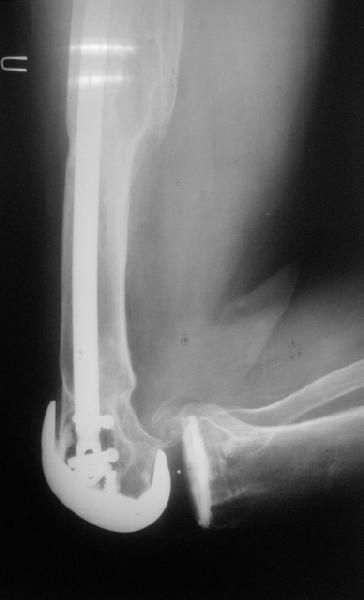

Видимо, самое "модное" на сегодня - малоинвазивный остеосинтез пластиной с угловой стабильностью. Распространенный вариант и закрытый интромедуллярный остеосинтез ретроградно. Хотя у нас было бы сделано антеградно - лешево и сердито, действительно малоинвазивно, в сустав не надо влезать. Нет риска прорезания порозной кости с миграцией в сустав, что возможно при ретроградном - гвоздь вводится через вырез в бедреннм компоненте, туда же может и вывалиться. А антеградный - упрется в протез. Как раз вчера заходил больной через полтора года после такой операции. Снимки в приложении.